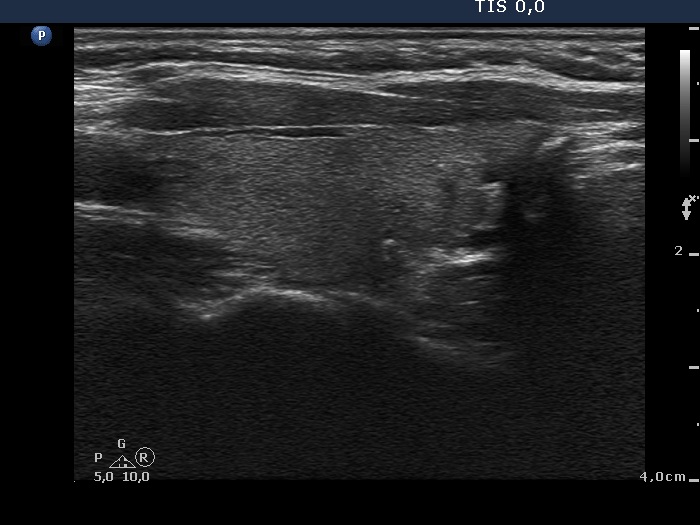

Subacute granulomatous thyroiditis - case 1285

Follow-up - 21 months after initial investigation (ultrasonographic picture 2)

Right lobe, longitudinal scan.